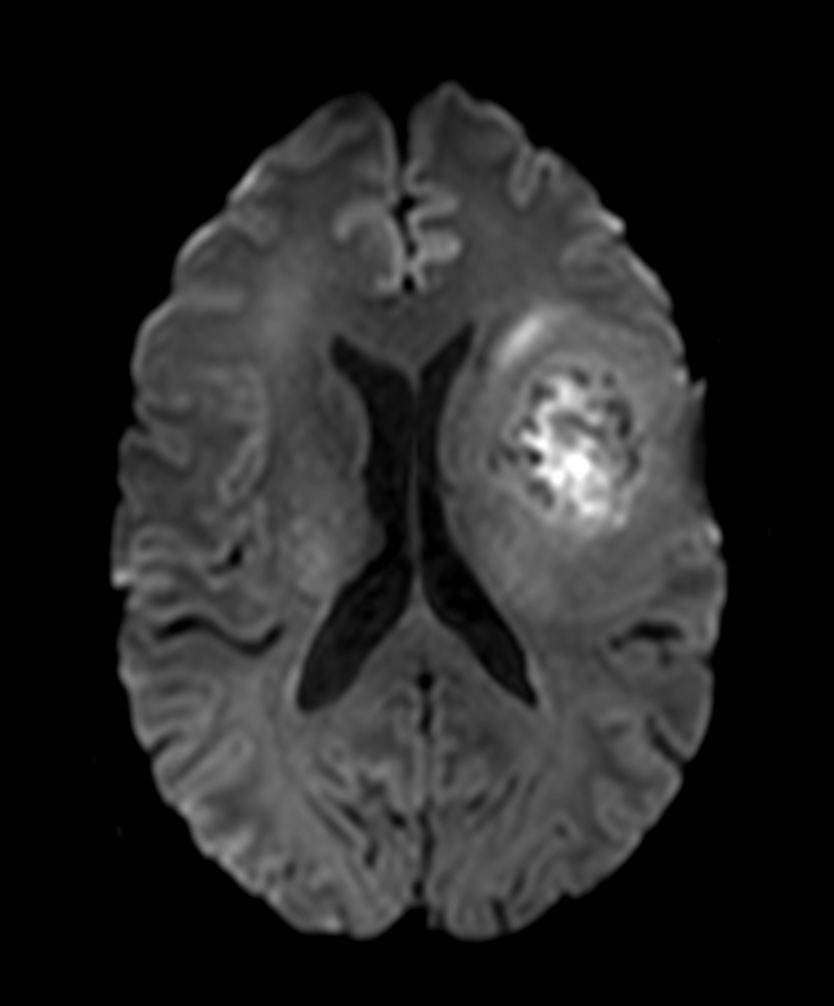

Axial T2w MultiVane XD